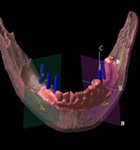

CT撮影

CT装置で撮影し、あごの骨の状態を診断します。

CTにて撮影したデータを、3次元画像解析システムにより、患者さんの神経や骨の状態を細部まで分析します。